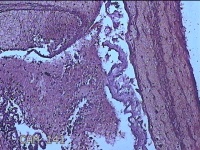

子宫腔内组织

性别

女

年龄

39岁

临床诊断

早期人工流产

一般病史

停经36天。

标本名称

大体所见

灰白暗红色不规则碎组织3x2.5x1.3cm一堆,未发现明显的绒毛样组织。

不具诊断价值。

在切片质量方面还需要加把劲。